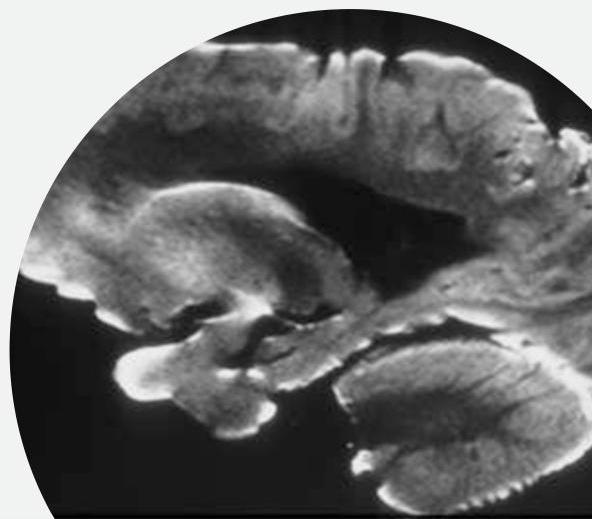

Pathophysiology of ALS: degeneration of UMN and LMN

Primary motor cortex

- Loss of cortical pyramidal motor neurons and gliosis

- Corticospinal tracts with variable patterns of degeneration

- Sclerosis and pallor of the corticospinal tract

- Precentral gyrus atrophy